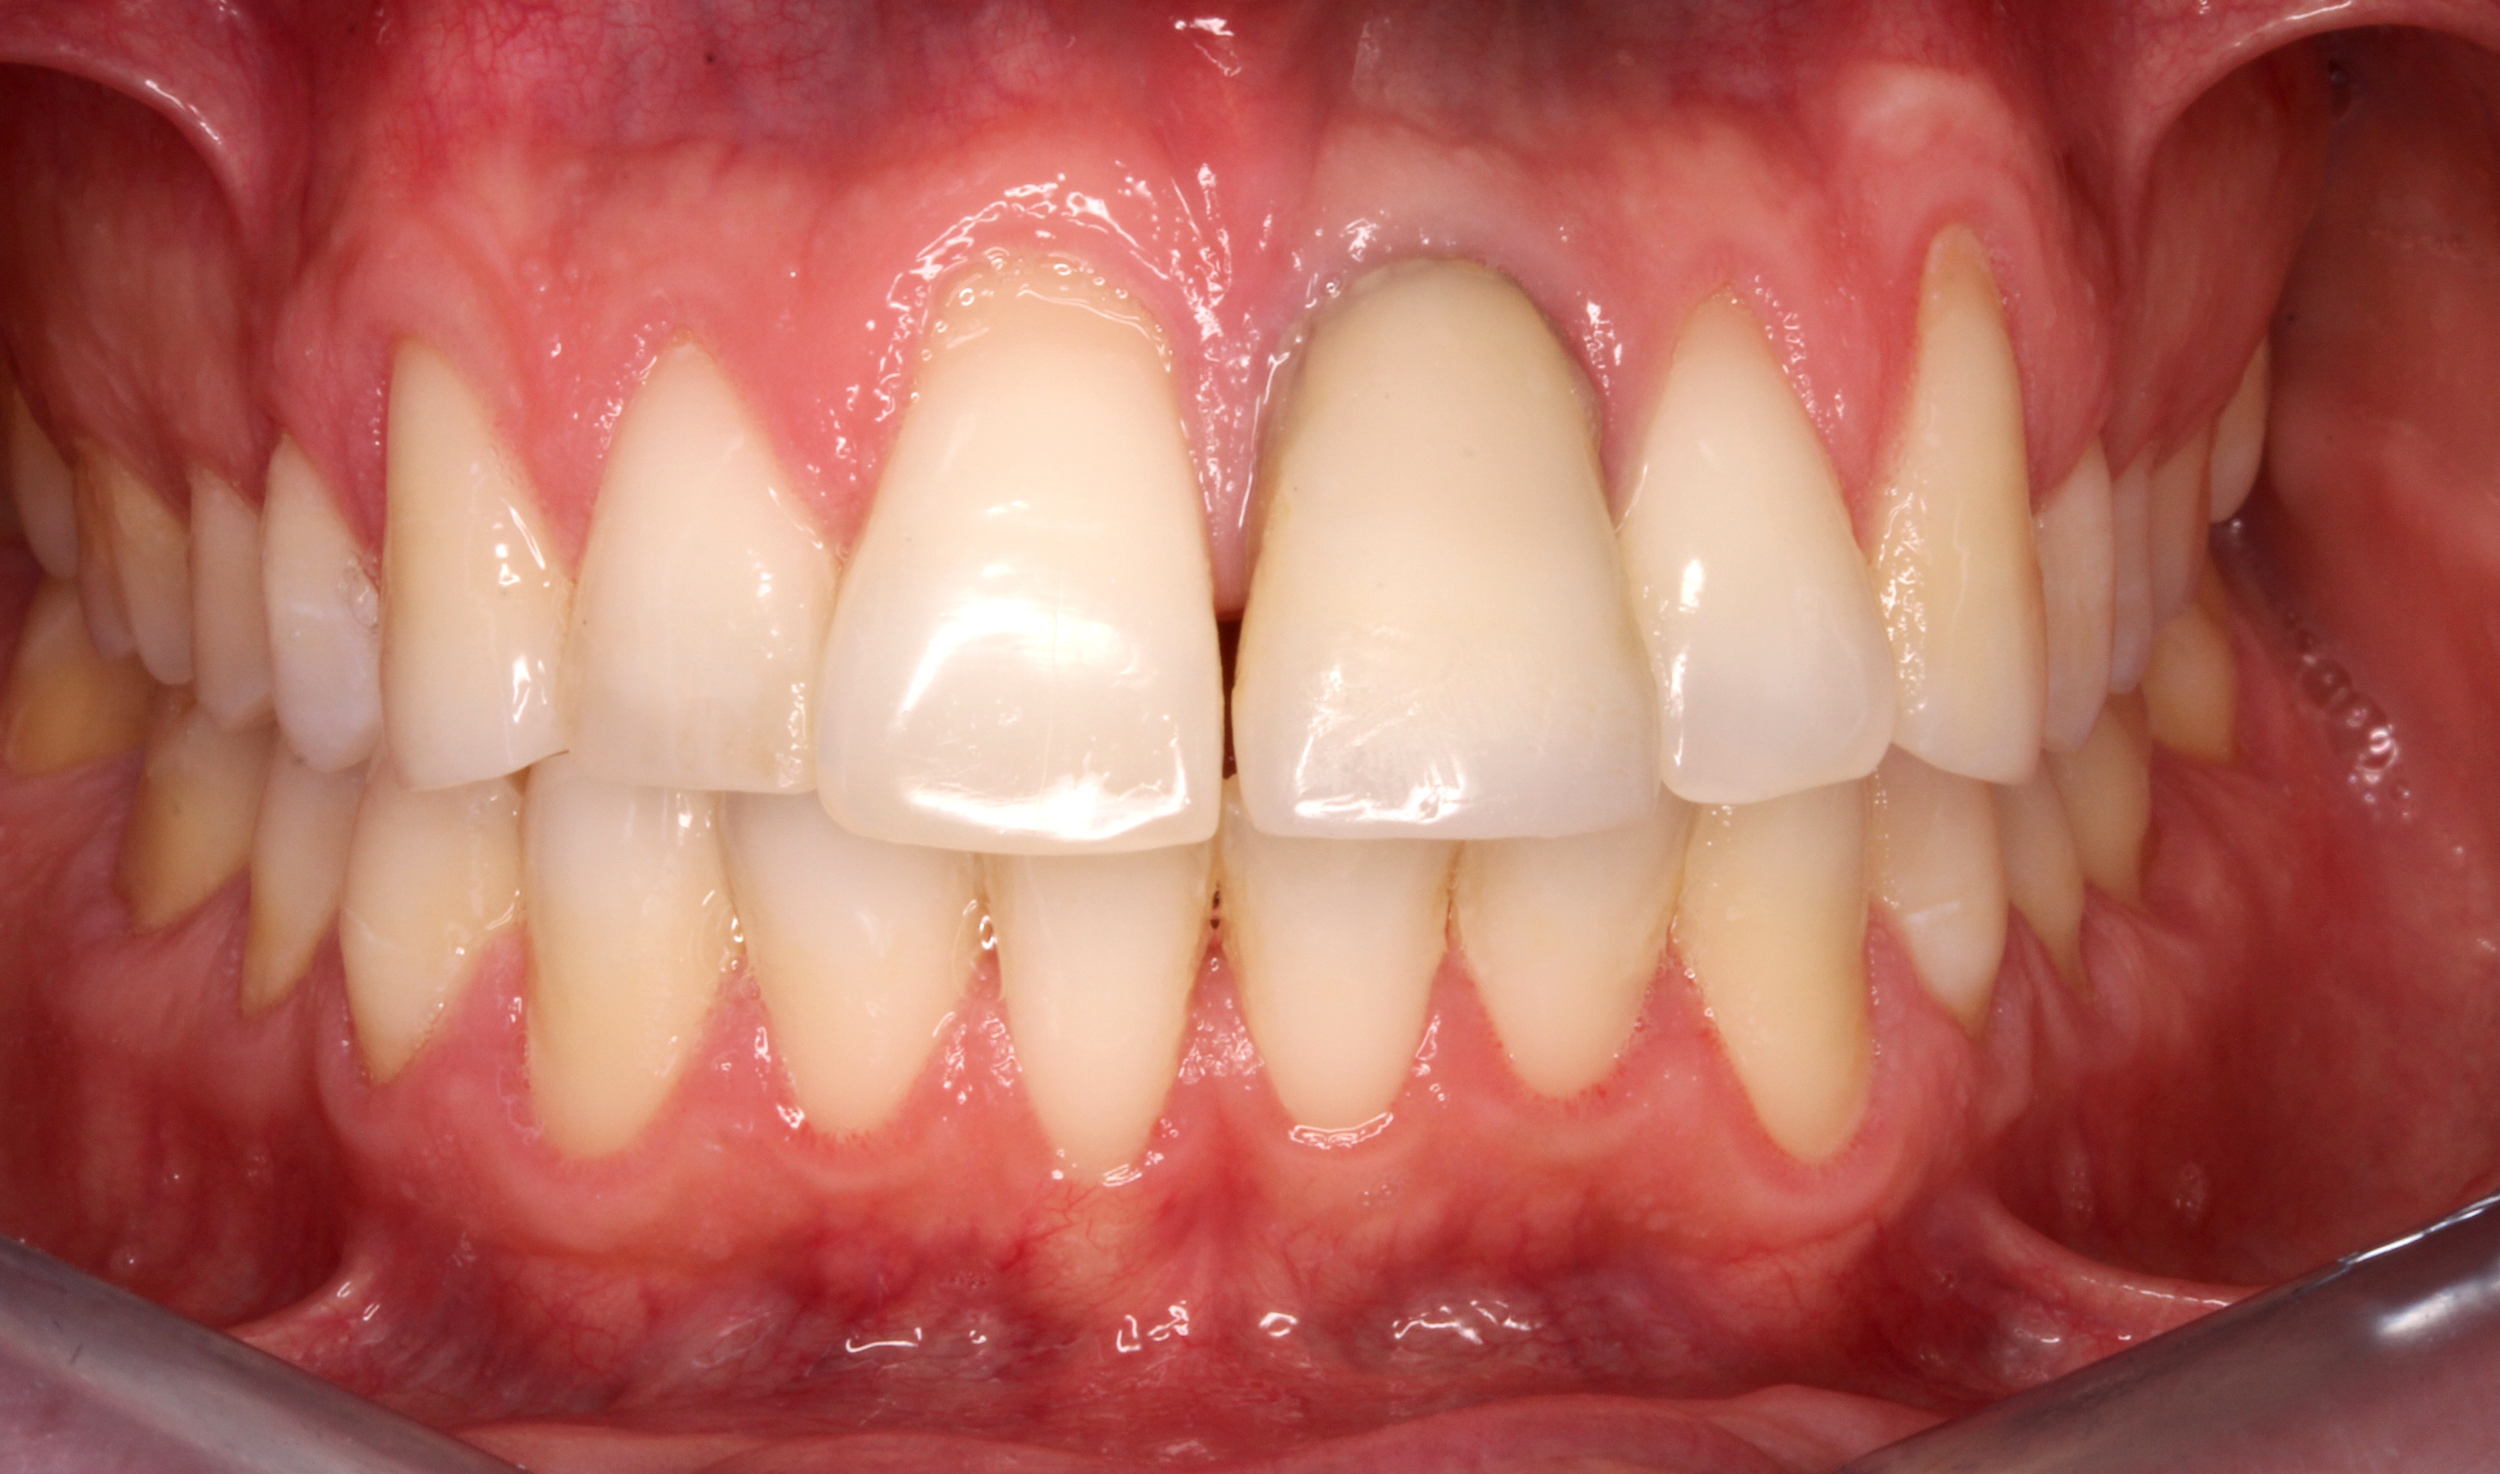

Caso 1

La paziente ha subito un trauma sugli elementi frontali nel 2000. I denti sono stati recuperati e riabilitati protesicamente con corone fisse sulle radici naturali. Dopo più di 20 anni, l’elemento 11 mostra segni di riassorbimento radicolare (tipico dei denti traumatizzati). Si procede con la sostituzione dell’elemento con un impianto singolo.

PRIMA

DOPO